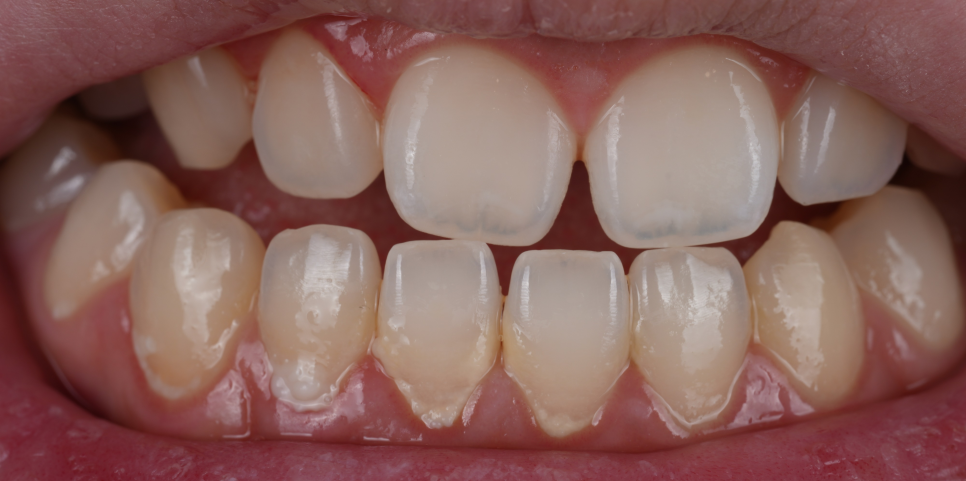

촬영 : 251030

치료를 마친 뒤 거울로 확인하더니 “이제 자신 있게 웃을 수 있겠어요!”라고 하시더라고요^^

이번 케이스는 단순히 틈이 있었던 게 아니라 치아 형태 자체가 항아리처럼 끝이 좁아져 실제보다 더 벌어져 보이던 상황이었는데요.

단순히 공간을 채우는 게 아니라 치아의 모서리 라인과 각도를 조정해 형태 자체를 교정하는 데 중점을 뒀습니다.

촬영 : 251030 / 251030

앞니 레진 치료는 ‘공간을 채운다’보다 ‘형태를 다시 만든다’는 개념에 가까워요.

이번 케이스처럼 치아 형태 때문에 벌어져 보이는 경우는 색감보다 곡선, 각도, 비율이 훨씬 중요해요.